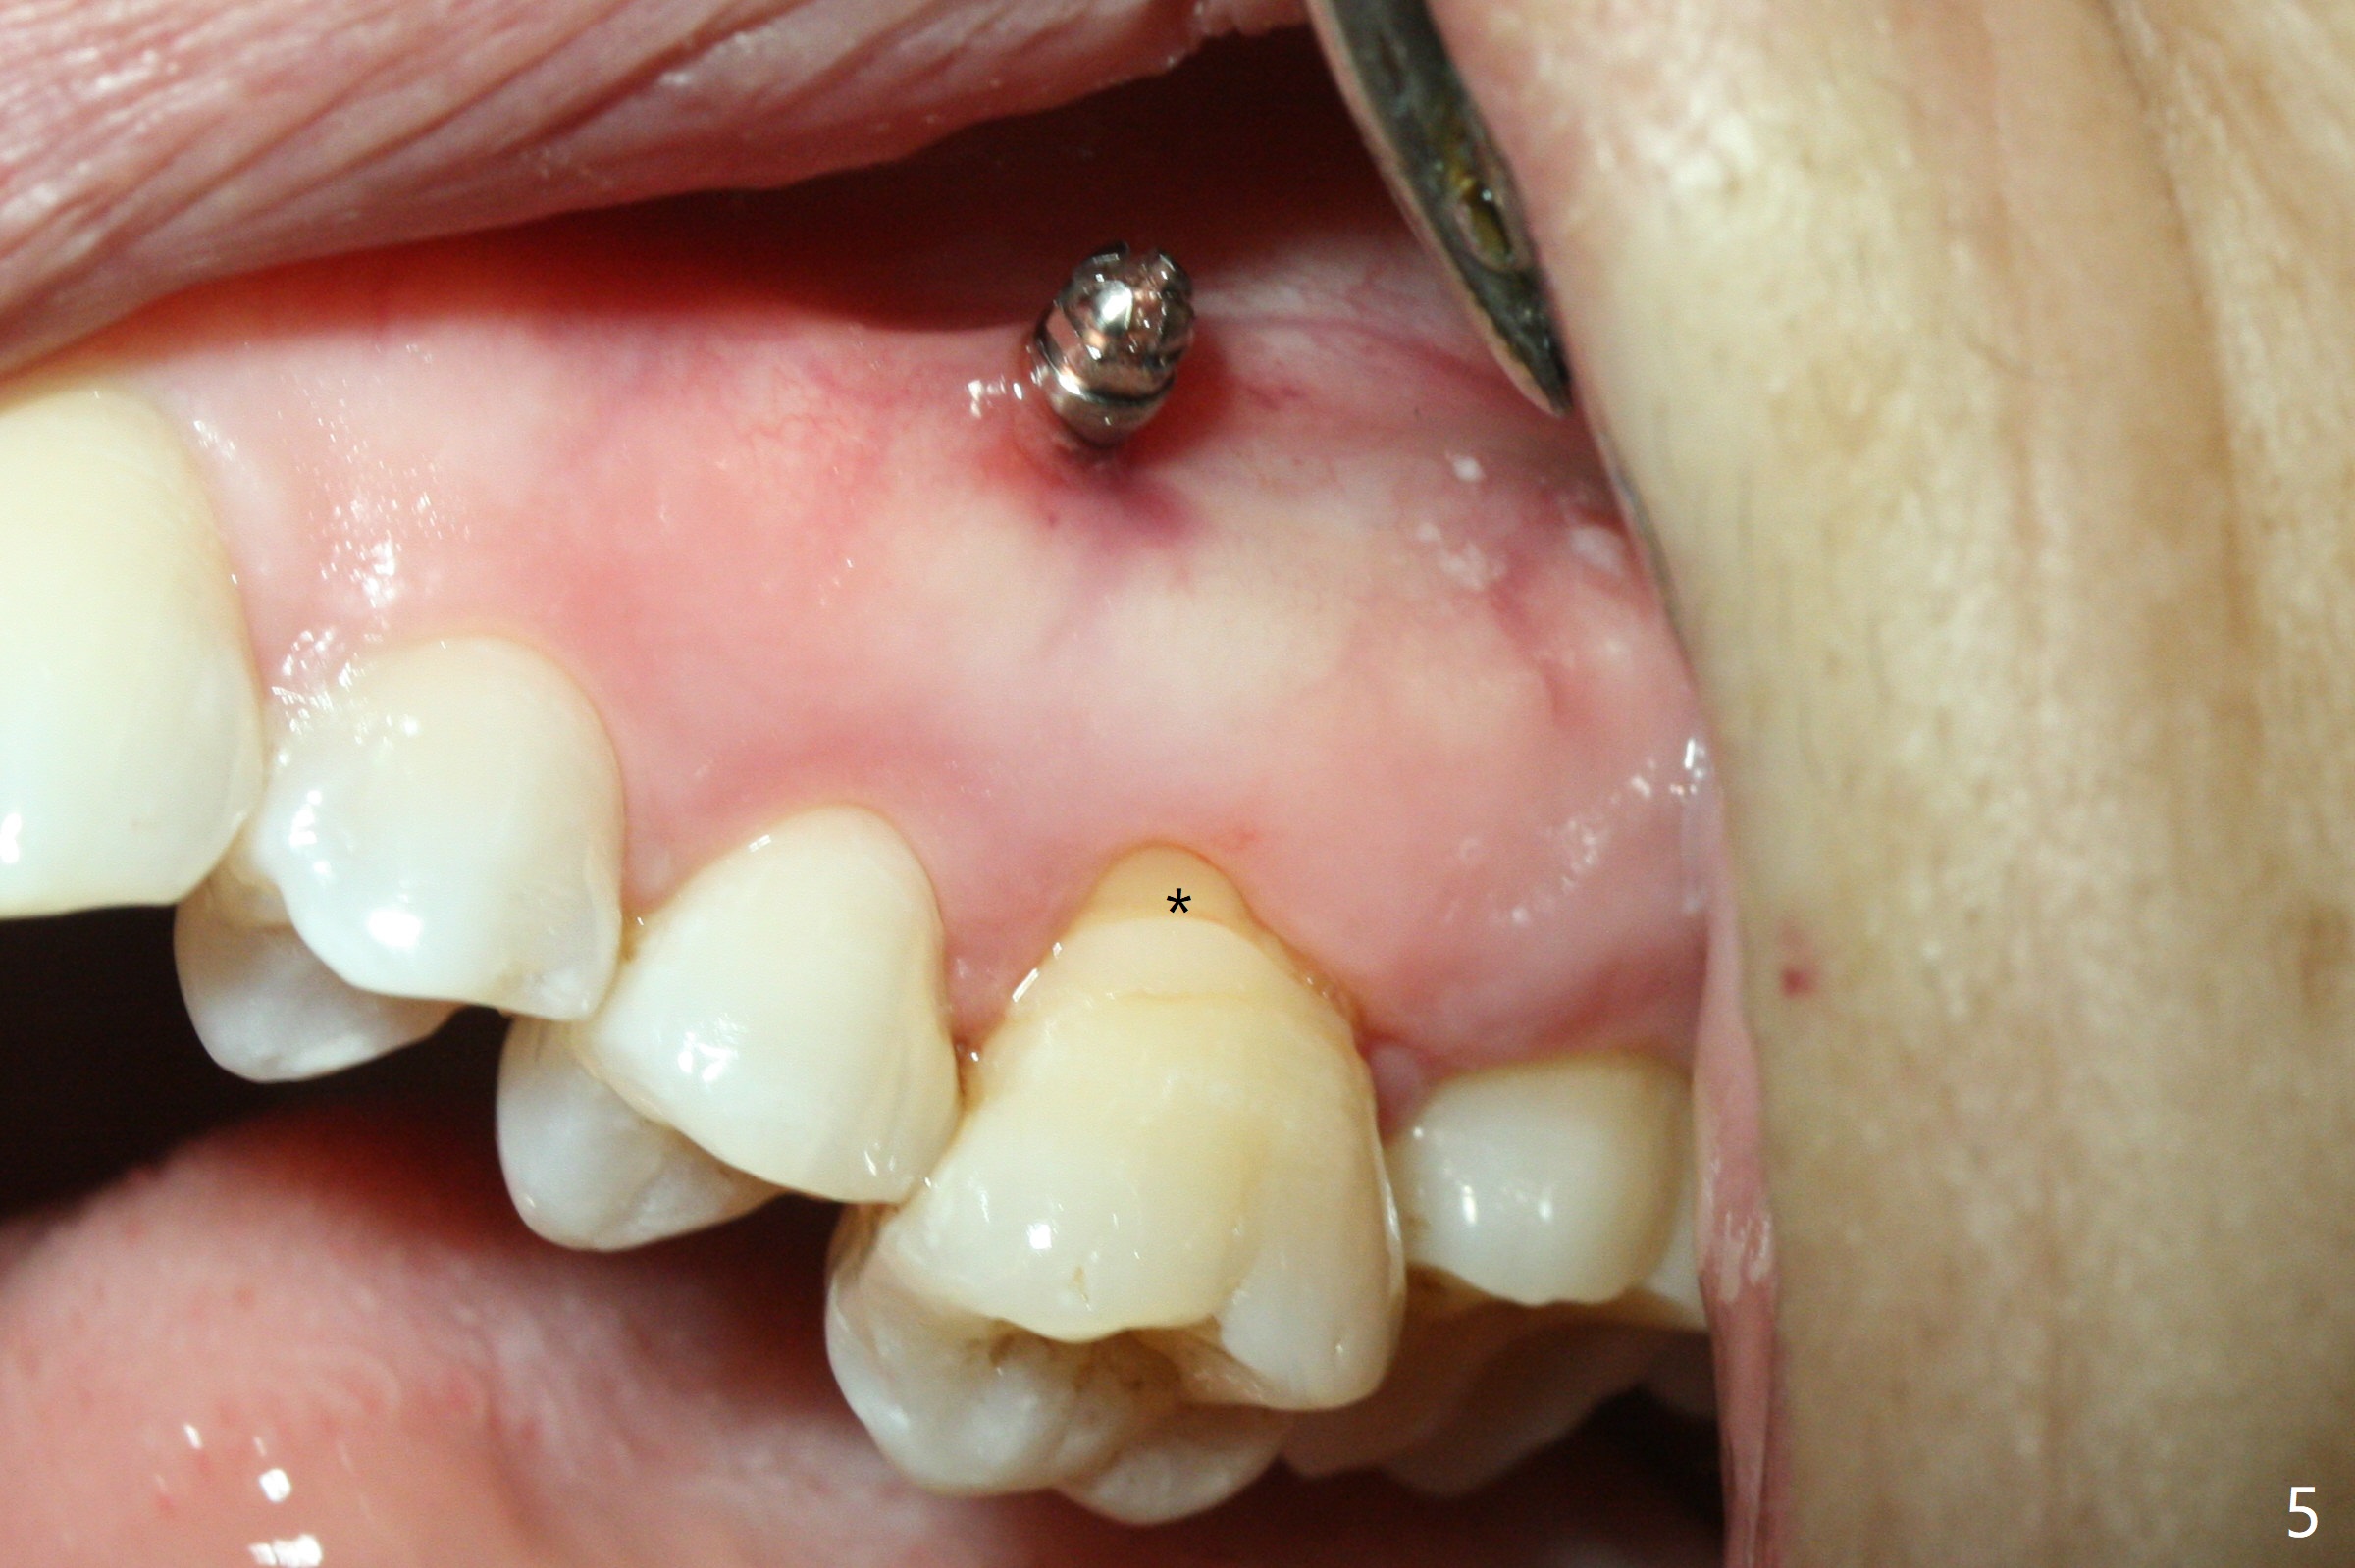

Fourteen days prior to implantation at #19 to replace a flipper (Fig.2), two minimplants are placed to intrude the supraerupted opposing tooth (#14, Fig.1). After use of minimal amount of local anesthetic (to keep proprioceptive in case root surface violation), the miniimplants are inserted ~ half of the length initially (Fig.3,4). The mesiobuccal (MB) one seems to be better positioned than the distopalatal (DP) one. When the implants are completely seated (Fig.5,6), three of PAs are taken, which suggests contact of the MB implant to the MB root of the tooth #14 (Fig.7 arrow). Immediately postop CT confirms approximation of MB and DP implants to the MB and P roots, respectively (Fig.8,9). The trajectory of these implants remain unchanged. Twelve days postop, the patient returns, uncomfortable with the palatal implant. After deep placement to bury the cuff (Fig.6) without local anesthesia (bone having no innervation), the patient feels better.